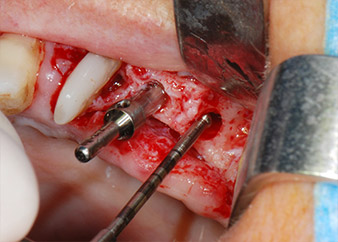

тотална загуба на кост и захват

Фиг. 2 и 3: След повдигане на ламбото, един месец след ендодонтския преглед и прилагане на цялостна периодонтална терапия в цялата уста, букалният корен на зъб 24 разкри тотална загуба на кост и захват.

Въпреки това, ние се придържахме към първоначалния си план да запазим и двата зъба като абатмънти за временен мост по време на 6-месечната остеоинтеграция на имплантите. При повторна интервенция, ситуацията трябва да се преразгледа. Първо, в опит да се овладее ендо-перио проблема, останалата повърхност на зъба е внимателно обработена с пиезохирургично оборудване (Piezomed, W&H, използван с накрайник S1 под формата на шпатула, първоначално проектиран за ерозия на латералната синусна стена) (Фиг. 4).

Фиг. 4: За да се съхрани зъбът като временен абатмънт, периодонциумът е изпилен с пиезохирургично оборудване...

букален апекс на зъб 24

Фиг 5: ... и букалният апекс на зъб 24 е обработен със същия инструмент (апикоектомия).